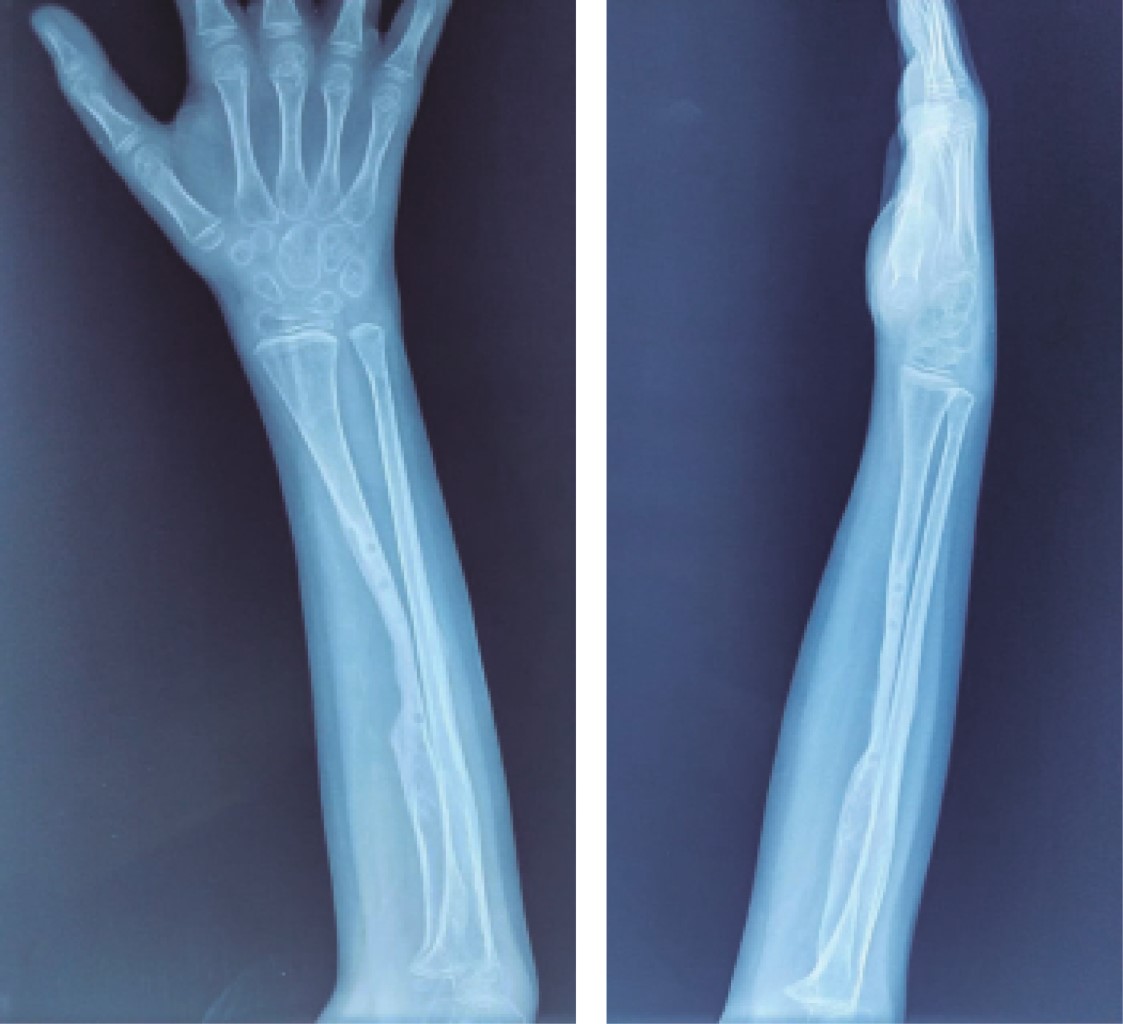

Introduction: the functions of vitamin D are very varied, from the regulation of cell proliferation, the modulation of the immune system, being the intestinal absorption of calcium, phosphorus, and magnesium one of the most important. Low levels of vitamin D are directly related to alterations in bone metabolism. Objective: to present the clinical case of a patient with a forearm fracture and vitamin D insufficiency, showing the complications that can occur in the bone consolidation process, as well as broadening the knowledge of this pathology. Clinical case: the case of a 7-year-old male patient is presented, who suffered a forearm fracture with a low-energy mechanism, evolving with delayed consolidation; there are important alterations of the bone structure after surgical management, when performing the endocrinological study, low levels of vitamin D are found, the bone changes are reversed when adequate levels of vitamin D are achieved. Conclusions: the clinical approach and surgical management in patients with fractures and suspected vitamin D disorders must be meticulous, given the potential complications that we may face.

Figure 3